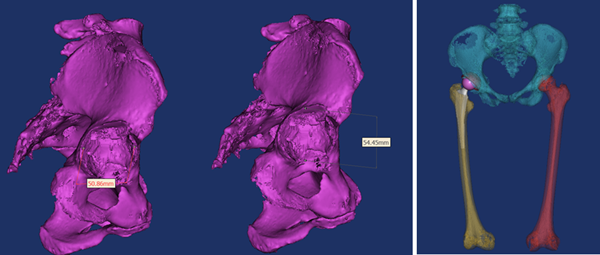

骨科关节置换手术,术前精准手术方案的制定是手术成功与否的关键。手术前,耿硕根据患者术前三维CT扫描数据,进行三维术前规划,精确测量患者相关参数,计算适合患者假体型号及测试假体安放位置,实现个性化定制手术方案,经过术前规划,刘阿姨右侧髋关节应当采用54mm G7髋臼杯,11号ML taper股骨柄,这套方案适合刘阿姨的生理解剖,使术后功能更加良好。